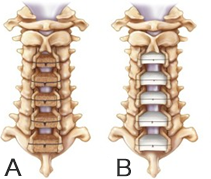

頚椎椎弓形成術(第3頚椎ー第7頚椎)後方からの模式図

A:自家骨を用いる場合

B:人工骨を用いる場合

頚椎症性脊髄症の中で脊椎内視鏡下手術の適応でないもの、後縦靭帯骨化症による脊髄症に対して頚椎後方から椎弓形成術(脊柱管拡大術)を実施しています。変形が高度のもの椎間が力学的に不安定なものに対しては最新の手術器械を使用しての固定術を併用しております。術後療法や入院期間は病態や術式により異なりますが、概ね2-4週間です。